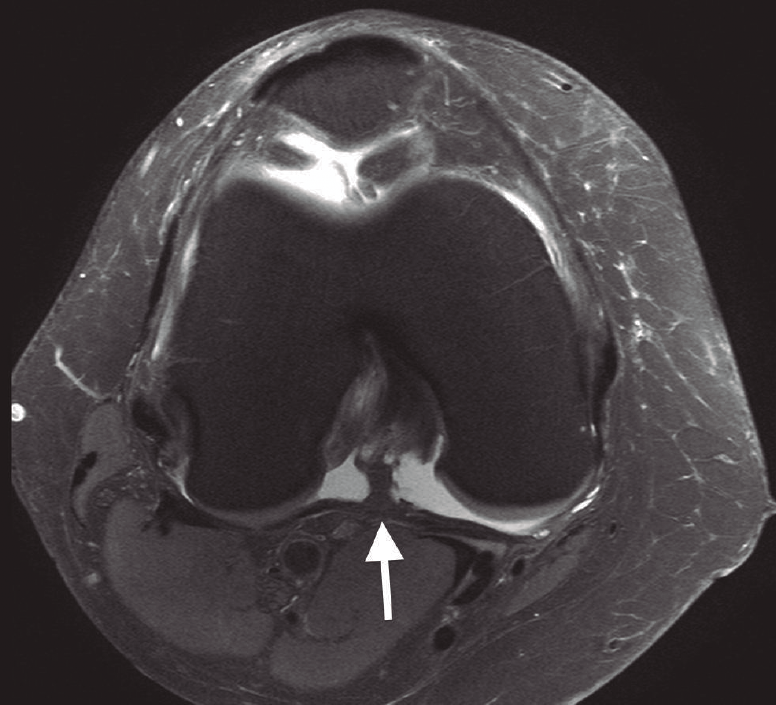

Figura 5. Corte axial de resonancia magnética de una rodilla derecha, donde se evidencia la presencia del septo o tabique posterior dividiendo la región posterior de la rodilla en dos compartimentos independientes. Flecha: septo posterior.

Los compartimentos PM y PL de la rodilla se encuentran independizados entre sí por un tabique o septo de forma triangular que se extiende entre la porción posterior del ligamento cruzado posterior y la cápsula articular posterior(33)(Figura 5). La creación de un portal “transeptal” consiste en la apertura parcial de este septo, permitiendo el libre paso de óptica e instrumental entre ambos compartimentos posteriores desde los portales PM y PL (Figura 6).